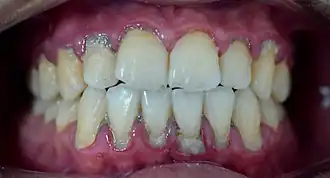

Heavy staining and calculus deposits exhibited on the lingual surface of the mandibular anterior teeth, along the gumline

Supragingival calculus formation is most abundant on the buccal (cheek) surfaces of the maxillary (upper jaw) molars and on the lingual (tongue) surfaces of the mandibular (lower jaw) incisors.[18] These areas experience high salivary flow because of their proximity to the parotid and sublingual salivary glands.